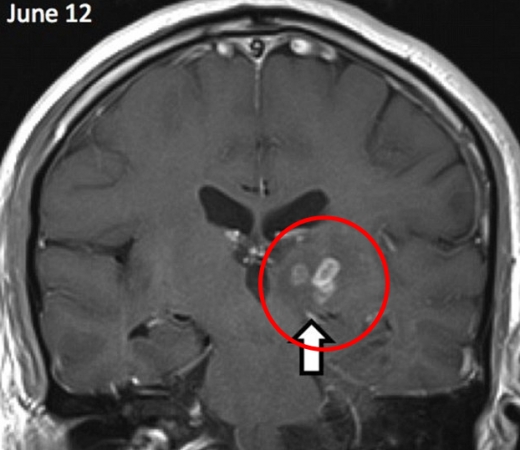

길이 1㎝의 촌충은 4년 전 환자의 머리에서 처음 발견했으며, 의료진은 최초 발견 이후 이 촌충이 뇌의 오른쪽에서 왼쪽으로 약 5㎝정도 이동한 것을 확인했다. 당초 기생충을 박멸하는 약물치료법을 시도했지만 기생충이 이에 저항하며 특별한 효과를 거두지 못했다.

수술을 집도한 에프로시니 그크라니아-크로차스 박사는 “이런 질병을 영국에서 보리라고는 예상하지 못했다”면서 “MRI 스캔을 통해 촌충이 있다는 것을 진단했지만 이에 대한 정확한 정보가 없어 4년간 섣불리 제거수술을 하지 못했다”고 설명했다.